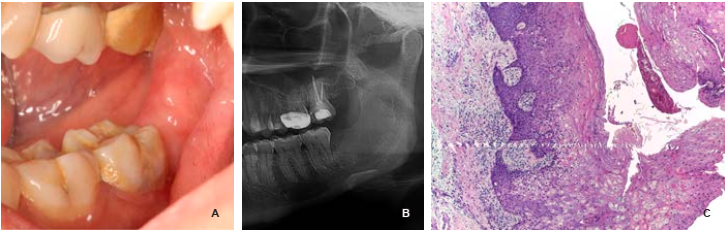

Reporte de caso: paciente femenino de 36 años de edad, se presentó en la Clínica de Medicina Bucal, de la División de Estudios de Postgrado e Investigación, en la Universidad Nacional Autónoma de México, por presentar un ligero aumento de volumen en la zona posterior inferior del lado izquierdo, con una evolución de entre ocho meses y un año aproximadamente. La paciente presentaba dolor en la zona sin presentar pérdida de la sensibilidad. A la exploración intraoral, los tejidos blandos eran de apariencia normal, acompañados de ausencia clínica del órgano dentario 38, en la zona retromolar izquierda se podía observar un aumento de volumen, de consistencia dura y doloroso a la palpación. La paciente refirió haberse sometido a la extracción quirúrgica del tercer molar inferior izquierdo 10 años atrás. No se encontró ningún otro padecimiento sistémico o antecedente de importancia para el padecimiento actual (Figura 1A-C).

Figura 1 A y B) Las fotografías extraorales iniciales muestran un ligero aumento de volumen en la región del ángulo mandibular. C) Intraoralmente se observó un discreto aumento de volumen en el área retromolar. D y E) Estudios de imagen previos a la biopsia. E) La tomografía computarizada reveló la expansión de las corticales óseas y el desplazamiento del conducto del nervio dentario inferior.

En el examen radiográfico se observó una área radiolúcida multilocular, la cual se extendía desde el cuerpo distal del segundo molar a la rama de la mandíbula, de aproximadamente 6 × 4 cm, con bordes bien definidos y escleróticos; junto con un fragmento radicular y coronal, probablemente del órgano dentario 38. La tomografía computarizada reveló una área hipodensa en el hueso mandibular, con expansión y adelgazamiento de las corticales lingual y vestibular (Figura 1D y E). Para el plan de tratamiento se decidió realizar una biopsia incisional con el diagnóstico presuntivo de KC odontogénico versus ameloblastoma.

El estudio histopatológico reveló una cavidad revestida por epitelio plano estratificado, con algunas zonas del estrato basal en empalizada, hipercrómaticas y otras con acantosis, exocitosis leucocitaria y áreas con hiperplasia arcoidal. Sin embargo, debido al severo infiltrado inflamatorio, las características distintivas del KC odontogénico se encontraban modificadas: la cápsula del tejido conjuntivo fibroso denso y bien vascularizado, también presentaba un infiltrado inflamatorio crónico linfoplasmocitario severo y difuso, con calcificaciones distróficas, cementículos y matriz osteoide. Por último, se emitió el diagnóstico de queratoquiste odontogénico con proceso inflamatorio crónico (Figura 2A y B).

Figura 2 A y B) Microfotografías de la biopsia inicial, hematoxilina y eosina; (A) 100x; (B) se puede apreciar el epitelio quístico paraqueratinizada, con un estrato basal en empalizada y núcleos hipercromáticos, una cápsula de tejido conjuntivo subyacente denso y fibroso, y un severo infiltrado inflamatorio, 400x. C) Abordaje quirúrgico a la cavidad quística. D) Colocación y fijación de drenaje tipo Penrose. E-G) Ortopantomografías de seguimiento. E) Un mes después del tratamiento quirúrgico. F) Dos meses después. G) Cuatro meses después.